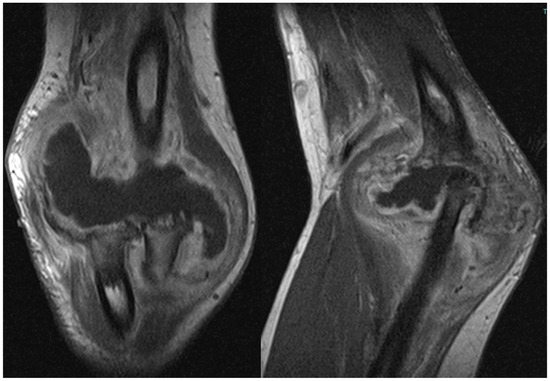

2.3. Further Investigations